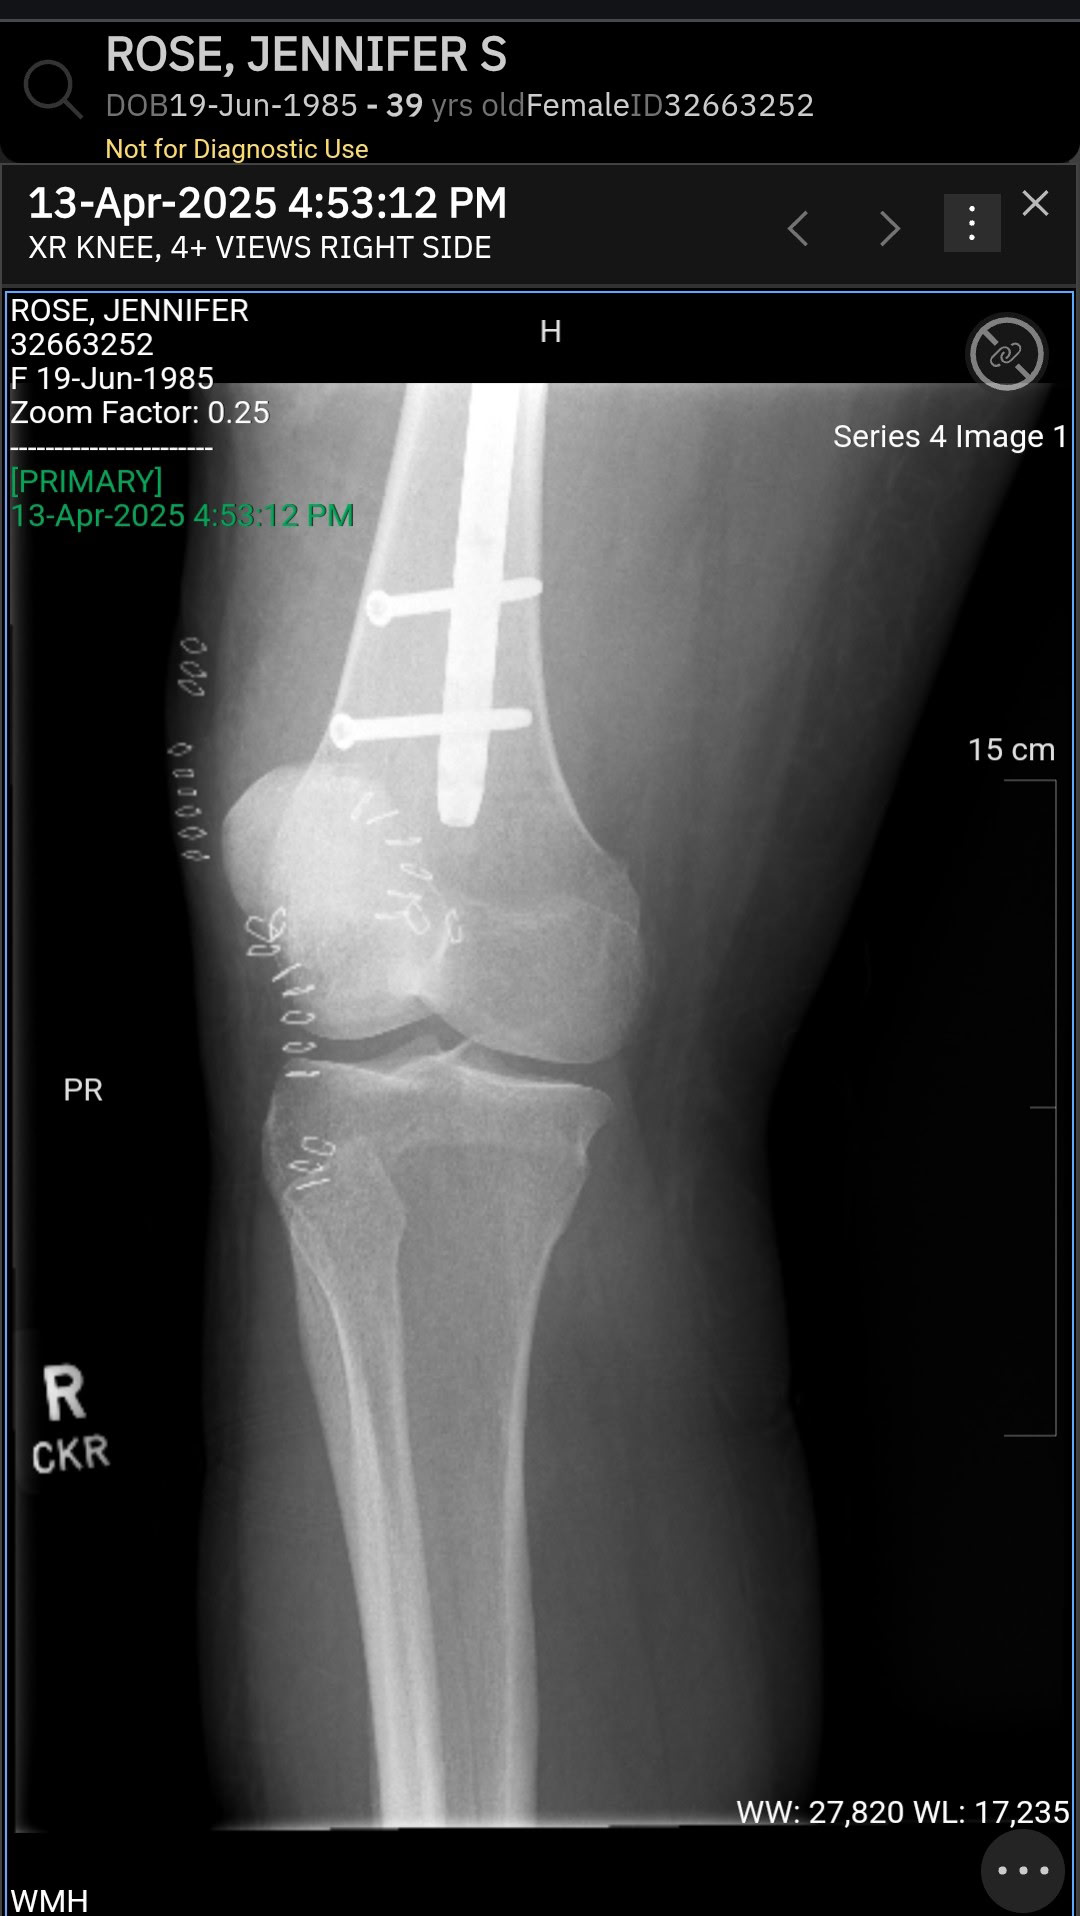

Unfortunately she was in an accident April 1. She was luckily saved by our firefighters using the jaws of life. She was then rushed into emergency surgery to save her leg and get a titanium femur put in. She stayed in the ICU for about a week, and the hospital as a whole the entire month of April.

Amazingly, she has pulled through, but has a long time for recovery. Doctors estimate she will need to heal for 6-12 months.

All the muscles in her leg and body are adjusting to this new titanium rod. It causes incredible pressure on the stitches, muscles and tissues surrounding. Balance is not something you automatically have, and she sorely misses the ability to catch herself.